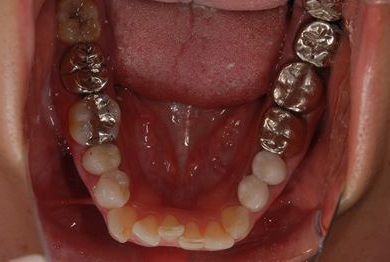

| 性別/年齢 | 女性 / 34歳 | ||||||||||||||||||||||||||||||||

| 主訴 | 現在痛みはなく、前歯の汚れを治したい。奥歯はブリッジを考えている。審美を考えているが、今治療をしたいというよりは、セラミックなど詳しいことがわからないので、計画や説明を伺いたい。 | ||||||||||||||||||||||||||||||||

| 治療方針 | 上前歯部分、セラミック治療にて審美的回復を行う。 | ||||||||||||||||||||||||||||||||

| 治療内容 | オールセラミッククラウン3本(オールセラミック用土台3本)、メタルボンドセラミッククラウン1本 | ||||||||||||||||||||||||||||||||

| 総治療費 | 562,800円 | ||||||||||||||||||||||||||||||||

| 治療期間 | 8ヶ月 |